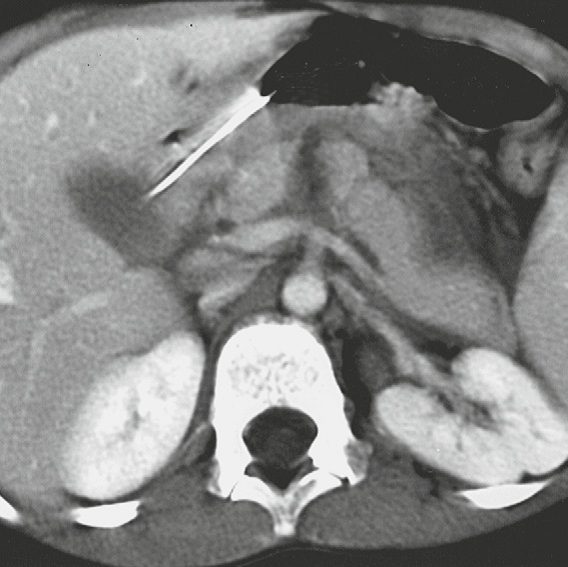

In Henoch-Schonlein purpura, some of the body’s small blood vessels become inflamed, which can cause bleeding in the skin, joints, abdomen and kidneys. HSP –> intussusception! (due to bowel wall bleed and thickening) - usually jejunal (as opposed to ileocecal) - usually long segments